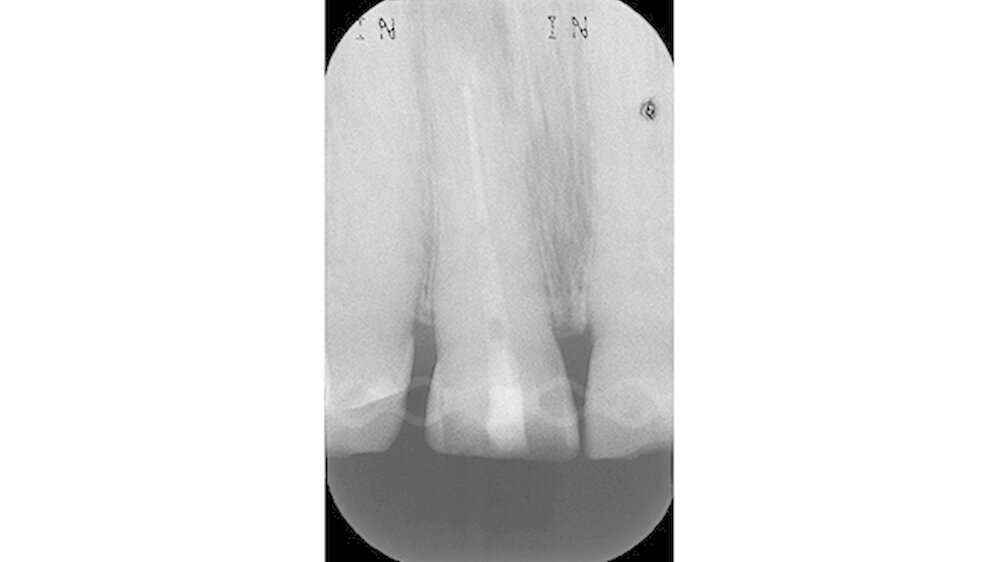

Bei der Vorstellung in der Poliklinik zeigte sich klinisch eine Schmelzfraktur auf der bukkalen Fläche des Zahns 11 (Abbildung 1). Die Messung der Taschensondierungstiefe (TST) ergab an dieser Stelle lokal begrenzt einen Wert von 7 mm (Abbildung 2). An allen übrigen Messpunkten lag eine physiologische TST von 3 mm vor.